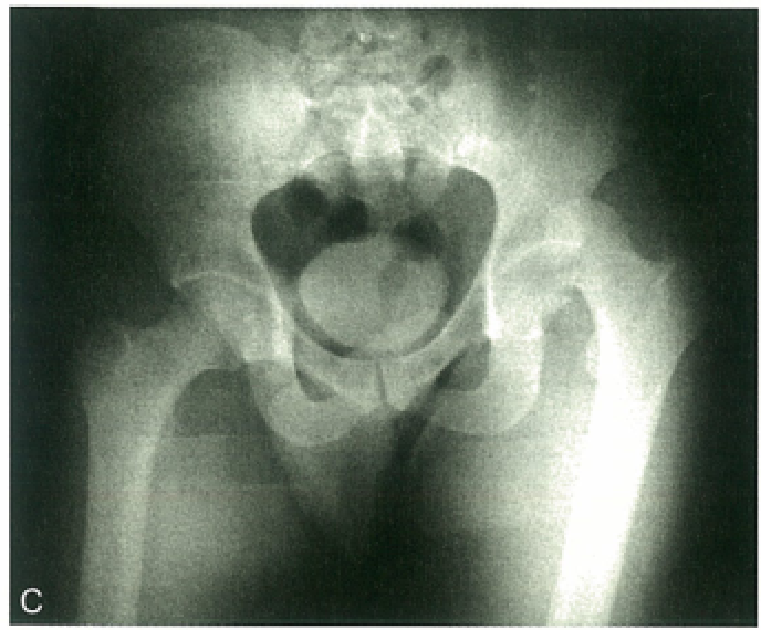

影像学检查X线片:股骨头位于髋臼的外上方、有无合并髋臼后缘骨折X线表现:后脱位股骨头变小,股骨头变大。后脱位时,小转子有可能因为肢体的内旋而不可见。前脱位时,小转子可因肢体的外旋而全部显现。

髋关节后脱位分类

Thompson和Epstein分型:I型:脱位伴有或不伴有微小骨折II型:脱位伴有髋臼后缘的孤立大骨折III型:脱位伴有髋臼后缘的粉碎骨折IV型:脱位伴有髋臼底部骨折V:脱位伴有股骨头骨折